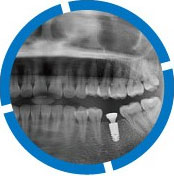

| 几乎适用所有缺牙类型 | 必须两侧邻牙健康、无缺失 | 几乎适用所有缺牙类型 | ||

| 无伤害 - 不磨损健康邻牙 强功能 - 咀嚼如真牙 更美观 - 色比真牙 |

需要磨掉旁边两颗邻牙 | 影响发音、恶心,咀嚼功能不佳 | ||

| 40年以上 | 10-20年 | 3-5年 | ||

| 正常清洁检查 | 定期复查还需注意咀嚼时避免用力过大 | 使用年限不长,容易老化变形 |